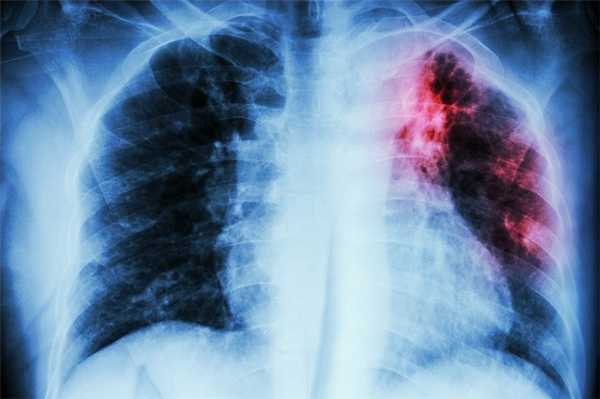

- Инструментальные методы. Проводится рентгенография грудной клетки в прямой и боковой проекции, выявляющая первичный очаг туберкулёза в лёгких. Поражение костей и других внутренних органов можно обнаружить с помощью КТ или МРТ.